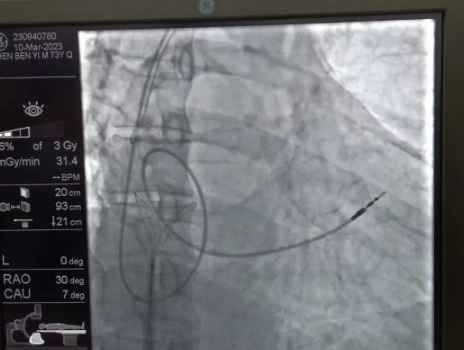

術(shù)中,孫書紅醫(yī)師首先切開起搏器囊袋,游離出起搏器脈沖發(fā)生器,發(fā)現(xiàn)起搏電極完全斷裂,連接于起搏脈沖發(fā)生器,殘端約10cm;考慮患者為起搏依賴患者,需再次植入新的起搏電極導(dǎo)線,穿刺了腋靜脈,放置導(dǎo)絲;同時,李偉杰教授穿刺了左、右股靜脈,于右股靜脈置入了”抓捕器”,左股靜脈備用臨時起搏通路,以防術(shù)中出現(xiàn)心跳驟停。為了準(zhǔn)確抓捕到心房內(nèi)的在逃起搏電極,李偉杰教授將導(dǎo)管室的X光機球管調(diào)整成了冠脈模式,這就意味著在抓捕過程中,醫(yī)生要比平時的手術(shù)“吃”更多射線……

在透視模式下,抓捕全憑醫(yī)生的經(jīng)驗與手感,一次次嘗試,一次次失敗,在場外觀摩手術(shù)的醫(yī)生同樣為李偉杰教授捏了一把汗,“找到了!”電子屏里抓捕器向在逃起搏電極“發(fā)起進(jìn)攻”,一把逮住并順利拔出一根長達(dá)58cm的起搏電極。